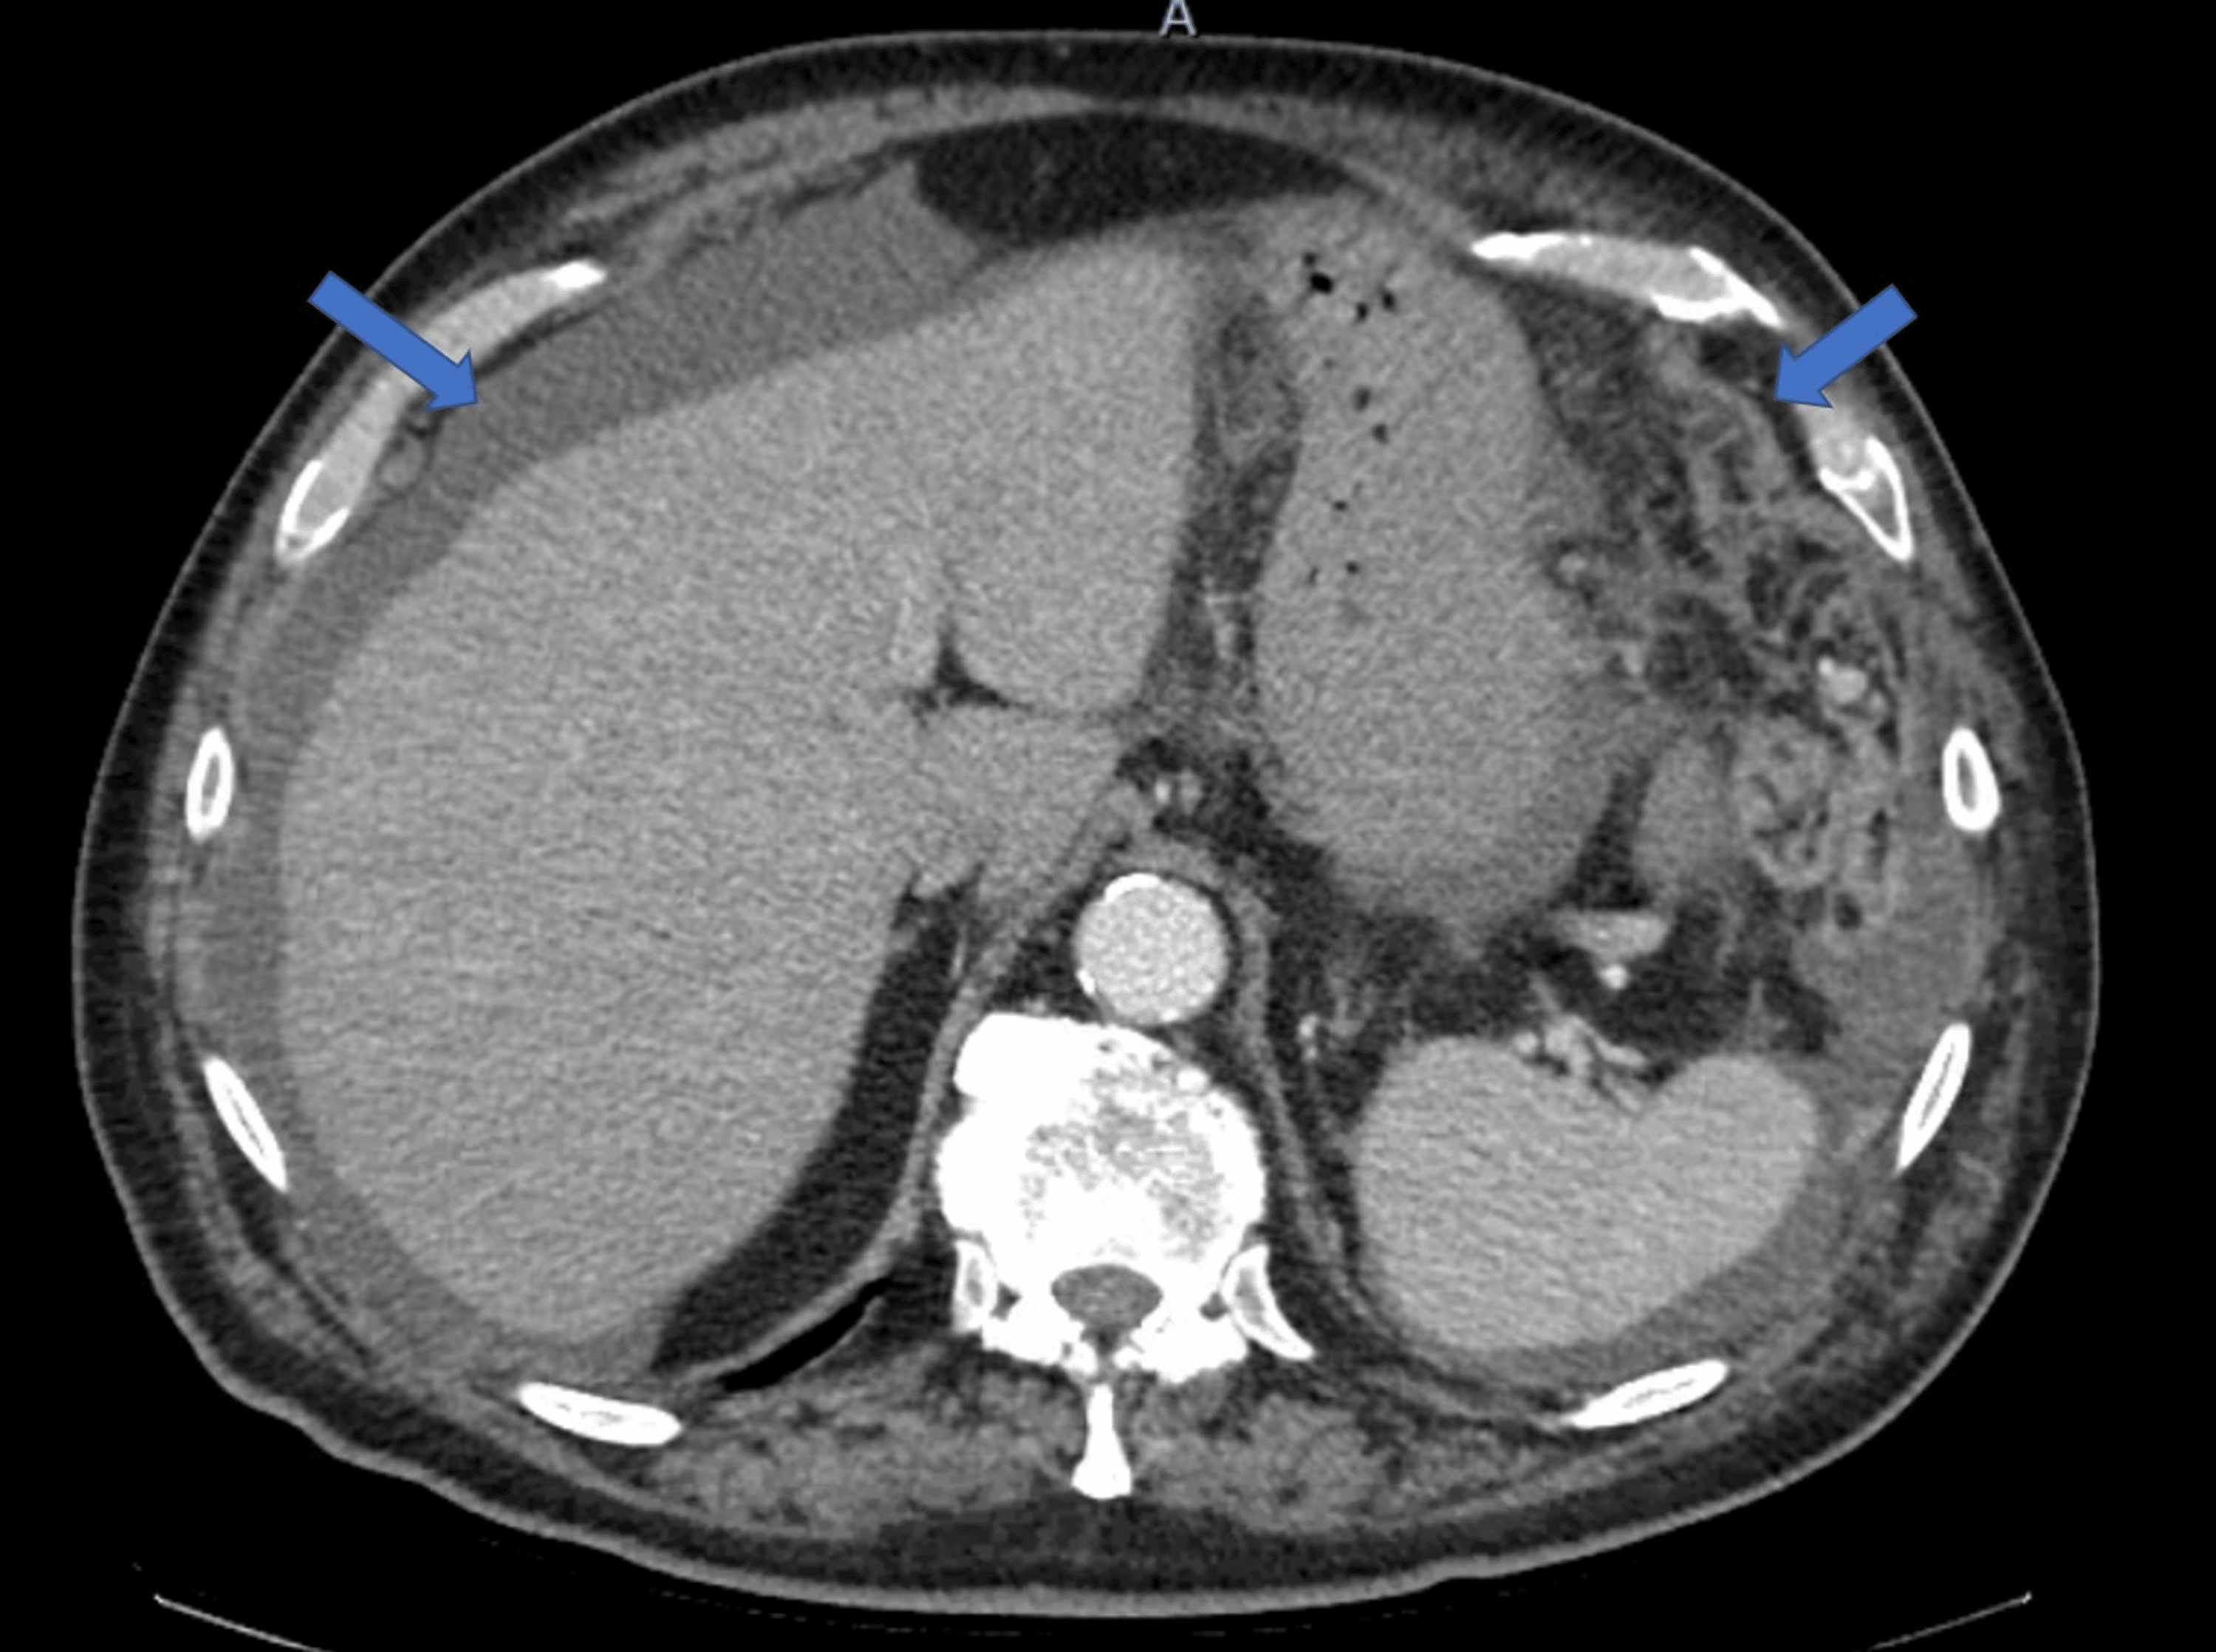

Patterns of peritoneal spread of tumor in the abdomen and pelvis

From www.wjgnet.com

Patterns of peritoneal spread of tumor in the abdomen and pelvis Abdominal Carcinomatosis Definition Peritoneal carcinomatosis is most often. Peritoneal carcinomatosis is a form of cancer that affects the peritoneum. The peritoneum is a thin membrane that covers most abdominal organs and lines the abdominal cavity. Cancer that has spread to the lining surfaces of the peritoneal (abdominal) cavity from ovarian cancer, primary colorectal cancer, appendiceal. It’s sometimes called primary peritoneal. Peritoneal cancer is. Abdominal Carcinomatosis Definition.